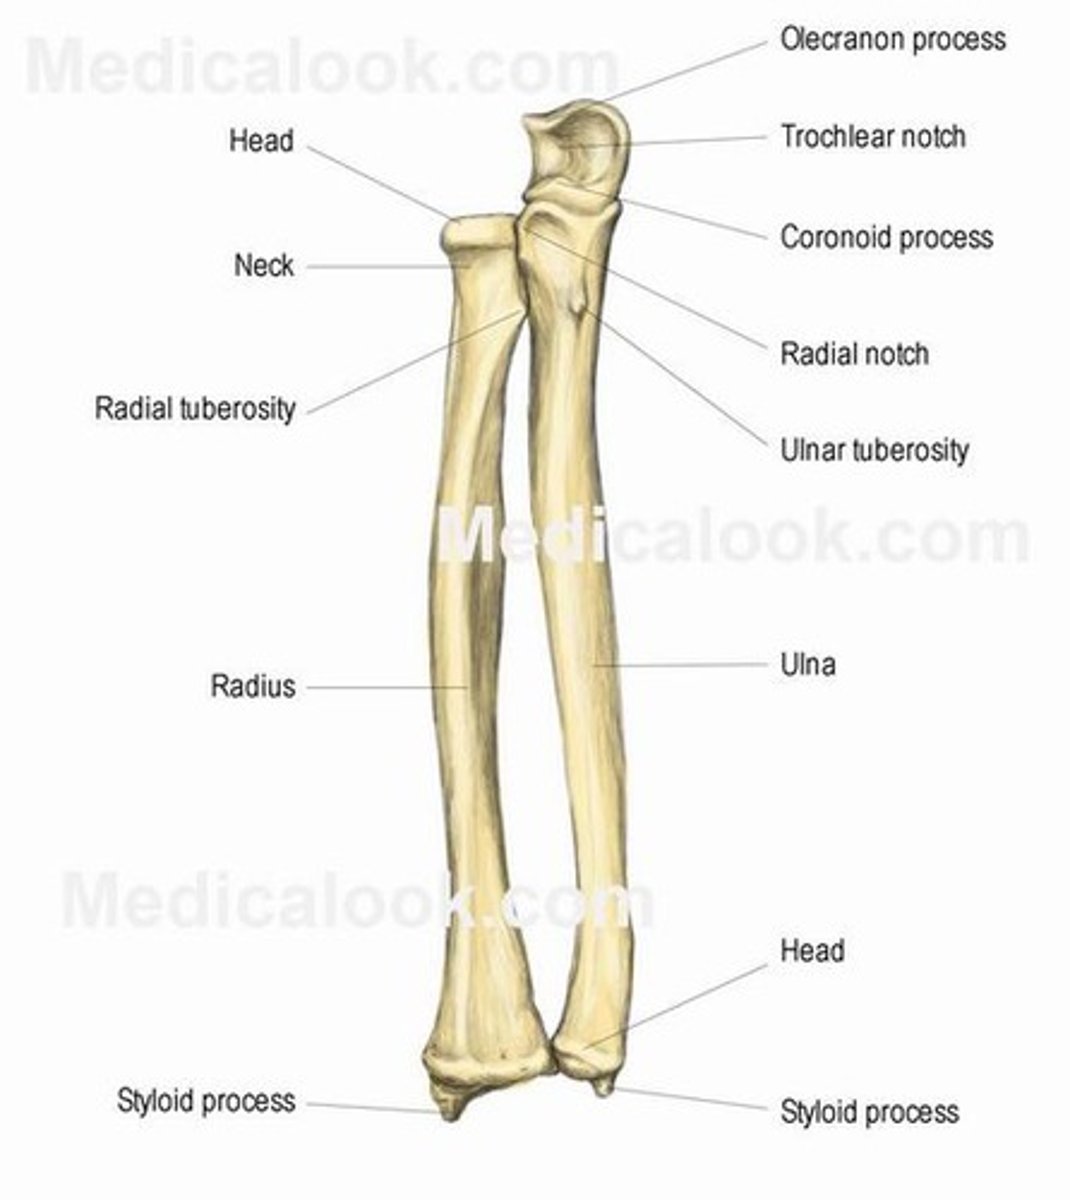

Bones of the forearm:

radius and ulna

Characteristics of the forearm:

- contains 2 bones

- radius can pivot on the ulna (supination and pronation) due to their parallel position

The ulna is the ___________ bone of the forearm

Stabilizing bone

Location of the ulna:

Medial and longer of the two forearm bones

Ulna articulation:

- Proximal end (more bulky) with humerus & head of radius

- does not form wrist distally

Features of the ulna:

- olecranon

- coronoid process

- ulnar tuberosity

- radial notch

- shaft

- head of ulna

- ulnar styloid process

Olecranon of the ulna:

Superior, most proximal portion.

What does the olecranon of the ulna articulate with?

Articulate with olecranon fossa of the humerus on its

anterior side

What is the function of the olecranon of the ulna?

Serve as a short lever for extension of the elbow

Coronoid process of ulna:

Inferior to the olecranon process

What does the coronoid process of the ulna articulate with?

Articulate with coronoid fossa of humerus on its anterior side

Ulnar tuberosity of the ulna:

Attachment for the brachialis muscle

Radial notch of the ulna:

Inferolateral to the coronoid process, receives the head of the radius

Shaft of the ulna:

Gets thinner distally

Head of the ulna:

Enlargement on distal part of the shaft

Ulnar styloid process:

Distal ending of the head of the ulna

What is the radius capable of doing?

Can pivot on the ulna (supination and pronation) due to their parallel position

Location of the radius:

Lateral & shorter of the forearm

What does the radius articulate with?

- Articulate with the ulna (proximally and distally)

- articulate with carpal bones on the distal side of radius

What structure of the upper extremities does the radius form?

Forms the wrist joint

What does the radius control in the forearm?

Controls supination and pronation

Head of the radius:

Articulates with the capitulum of humerus and with the radial notch of the ulna

Neck of the radius:

Inferior to the head

Shaft of the radius:

Gets thicker distally opposite to the ulna

Ulnar notch of the radius:

Articulates with the head of the ulna

Radial styloid process of radius:

Distal ending on lateral side of the shaft of the radius